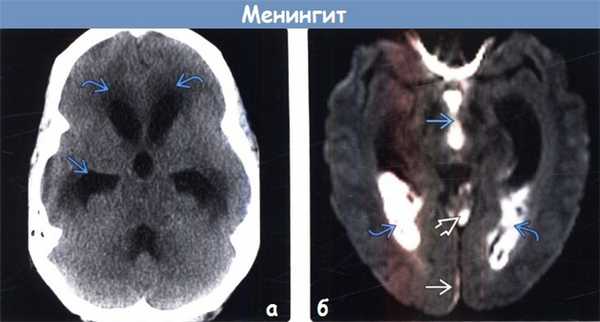

(а) Бесконтрастная КТ, аксиальный срез: у младенца борозды конвекситальной поверхности левого полушария головного мозга дифференцируются неотчетливо, что обусловлено воспалительной экссудацией, вызванной бактериальным менингитом. Заполненные гноем борозды практически изоденсны по отношению к нижележащей мозговой ткани, что затрудняет их обнаружение до тех пор, пока вы не сравните их с нормальными заполненными СМЖ бороздами правого полушария головного мозга.

(б) КТ с контрастированием: у того же пациента слева определяется интенсивное контрастирование экссудата, полностью заполняющего борозды.

(а) Бесконтрастная КТ: у пациента с пневмококковым менингитом определяется сообщающаяся гидроцефалия с понижением плотности мозговой ткани в перивентрикулярных отделах, что обусловлено перивентрикулярным интерстициальным отеком.

(б) МРТ, ДВИ, аксиальный срез: у этого же пациента наблюдаются осложнения менингита. Ограничение диффузии наблюдается в III желудочке и затылочных рогах боковых желудочков, что обусловлено вентрикулитом. В парасаггитальном отделе правой затылочной области присутствует непротяженная субдуральная эмпиема. Обратите внимание на повышение интенсивности сигнала на ДВИ, обусловленное экссудатом в верхней мозжечковой цистерне.